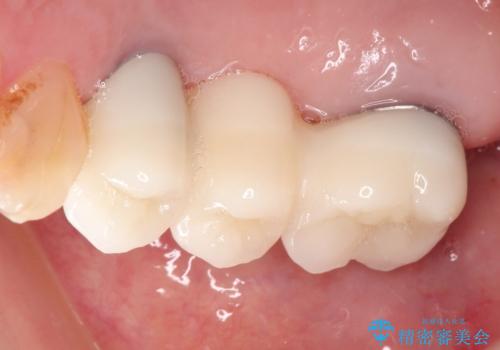

右の上下の歯を抜歯してインプラントを埋入して、かぶせ物を装着する計画としました。

右側のかみ合わせを回復するには、インプラントか入れ歯のどちらかの方法で治療する必要があました。

治療方法について十分な説明を行い、インプラント治療を選択されました。